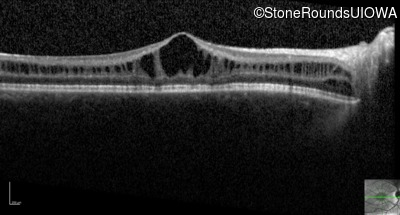

Optical Coherence Tomography - Right - 20/63 -2

Exemplar / OCT Stack